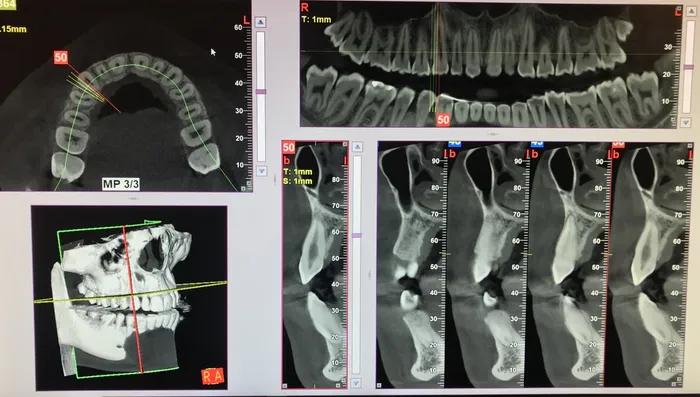

Se un dente è colpito da carie profonda o da un trauma che causa una pulpite (dolore fortissimo e continuo) o che determina la necrosi (morte) del dente con presenza di segni indiretti come i “granulomi”, ossia lesioni all’apice del dente valutate grazie a indagini radiografiche,

ll primo passaggio del trattamento, dopo l’anestesia e l’isolamento del campo operatorio con la diga di gomma, consiste nel raggiungere la camera pulpare del dente, dove è contenuto il nervo: vengono localizzati i canali radicolari che sono molto piccoli e i sistemi ingrandenti aiutano enormemente il dentista in questa fase. Successivamente, tramite strumenti manuali e rotanti e con l’utilizzo di disinfettanti, il nervo e il materiale infetto vengono rimossi. Il passaggio successivo è l’otturazione tridimensionale dei canali radicolari e l’avvenuta chiusura viene valutata con una radiografia, in cui si va a verificare che il materiale da otturazione giunga esattamente all’apice del dente.

Talvolta un dente devitalizzato necessita di ritrattamento che verrà impostato in maniera ortograda cioè con le stesse modalità con le quali è stato trattato la prima volta. Se vi fossero ostacoli alla sua buona riuscita si potrà ricorrere alla chirurgia endodontica, con accesso chirurgico diretto all’apice del dente per effettuare la resezione ed asportazione dell’apice stesso e provvedere alla otturazione retrograda del canale radicolare.